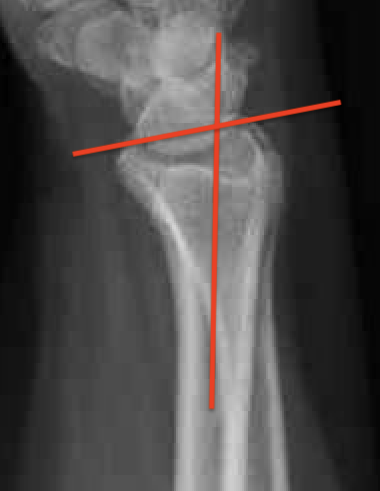

Radial angles

| Volar tilt mean 11° | Radial inclination mean 22° | Radius mean 11 mm longer than ulna |